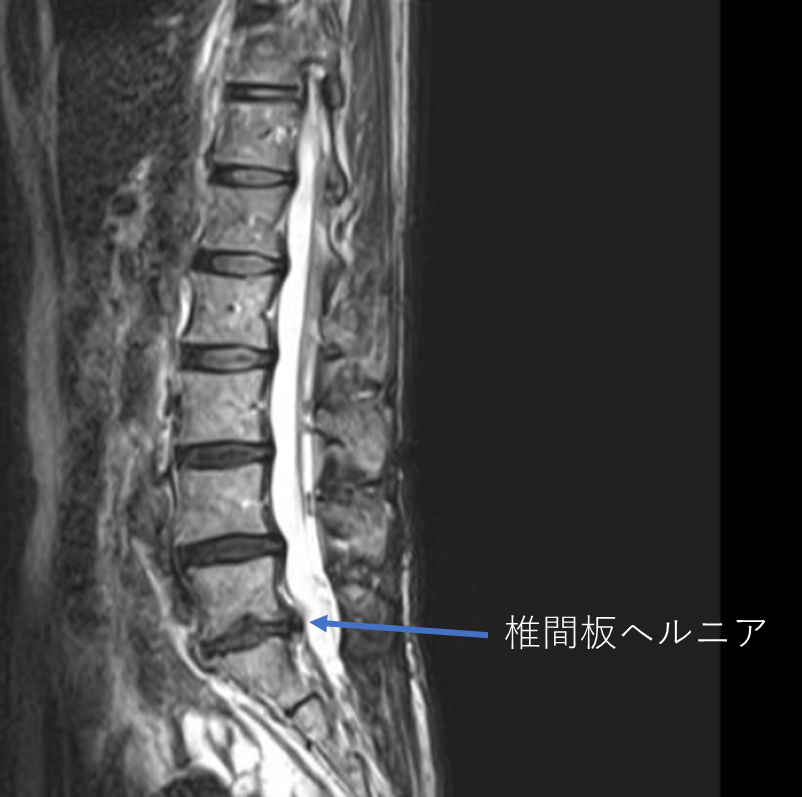

画像及び所見について

- L3/4,4/5,5/s-椎間板変性

- L5/s-椎間板ヘルニア

以上の事が画像上認められます。

・L5/s-椎間板ヘルニアを認め、症状を鑑みると主症状の原因の可能性が高い